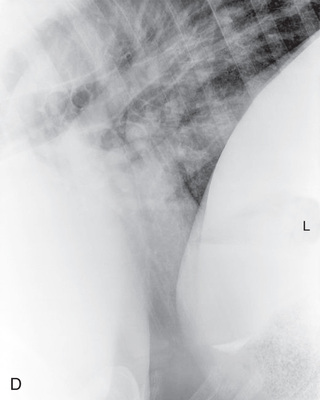

| Thorax | Lateral (Fig. 24.60) | Affected side | Horizontal beam on opposite side. | See comments later for specifics: | Patient standing. Portable unit not powerful enough. |

| Abdomen | Lateral (Fig. 24.61) | On side (most lesions on midline). | Opposite side. | Last rib for small horses: | Multiple laterals required for larger patients. |